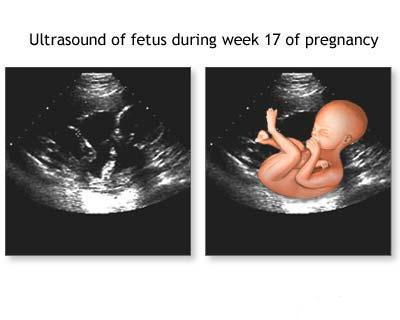

Aplicatia ecografiei in obstetrica